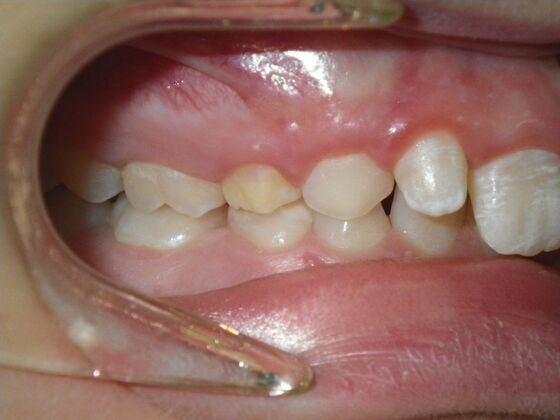

This patient does not like his anterior deep bite and the flaring of the right lateral incisor as well as anterior spacing. The solution was to correct his Class II molar relationship, Division II and deep anterior bite and close spacing as much as possible with addition of composite restorations on distals of lateral incisors. We began with utility archwires, eventually correcting Class II molar with distalizing appliance, and continued with final tip and torque. All that is left now is to ad composite to distals of upper lateral incisors.